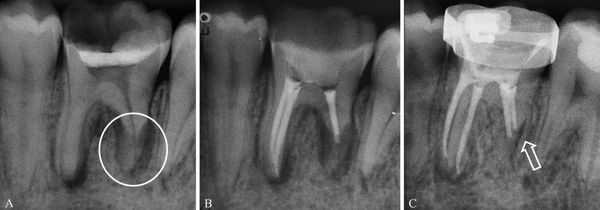

(Слева) На панорамной рентгенограмме у пациента с двухлоронним передним вывихом визуализируется правый мыщелок, смещенный кпереди и кверху относительно сулавного возвышения. Обратите внимание на явный передний открытый прикус, в то время как моляры находятся в окклюзии.

(Справа) На панорамной рентгенограмме у этого же пациента определяются аналогичные изменения слева. Открытый прикус обусловлен неправильным передним положением мыщелка, контакт задних зубов - его верхним положением.

2. Рентгенография при вывихе височно-нижнечелюстного сустава (ВНЧС):

• Радиографические признаки:

о Передне-верхнее положение мыщелков по отношению к суставному возвышению

• КТ в костном окне и КЛКТ:

о Хронический вывих: атрофия суставного возвышения и уплощение суставной ямки

(Слева) На рентгенограмме в боковой проекции у этого же пациента определяется прогнатическое положение нижней челюсти и открытый передний прикус вследлвие передне-верхнего смещения мыщелков нижней челюсти.

(Справа) На сагиттальной КЛКТ правого и левого мыщелков у этого же пациента определяется, что мыщелки расположены спереди и сверху относительно сулавных возвышений. Обратите внимание, что мыщелки имеют нормальную форму, а кортикальная плалинка не изменена.